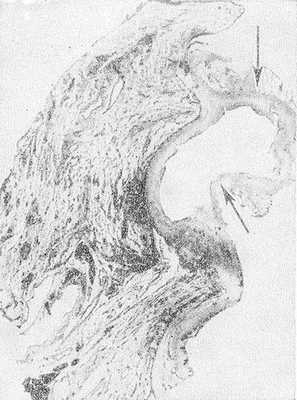

Основанием для такого подхода явилось не только стремление к выполнению функционально-щадящих вмешательств, но и проведенное собственное морфологическое исследование, которое показало, что поражение стенки мочевого пузыря при прорастании колоректальной опухоли в большинстве наблюдений не выходит за пределы видимых границ опухоли. Это позволило нам выполнять субтотальную резекцию мочевого пузыря даже при расположении опухоли вблизи мочепузырного треугольника. Срочное гистологическое исследование линии резекции мочевого пузыря подтверждало отсутствие в ней опухолевых клеток.

Все это позволило нам прийти к заключению, что показания к цистэктомии при прорастании рака толстой кишки в мочевой пузырь зачастую расширяют, основываясь на показаниях к таковой при первичном раке мочевого пузыря, характеризующемся мультифокальным поражением слизистой [9]. При прорастании стенки мочевого пузыря раком толстой кишки иная морфология опухоли определяет другой характер поражения стенки мочевого пузыря.